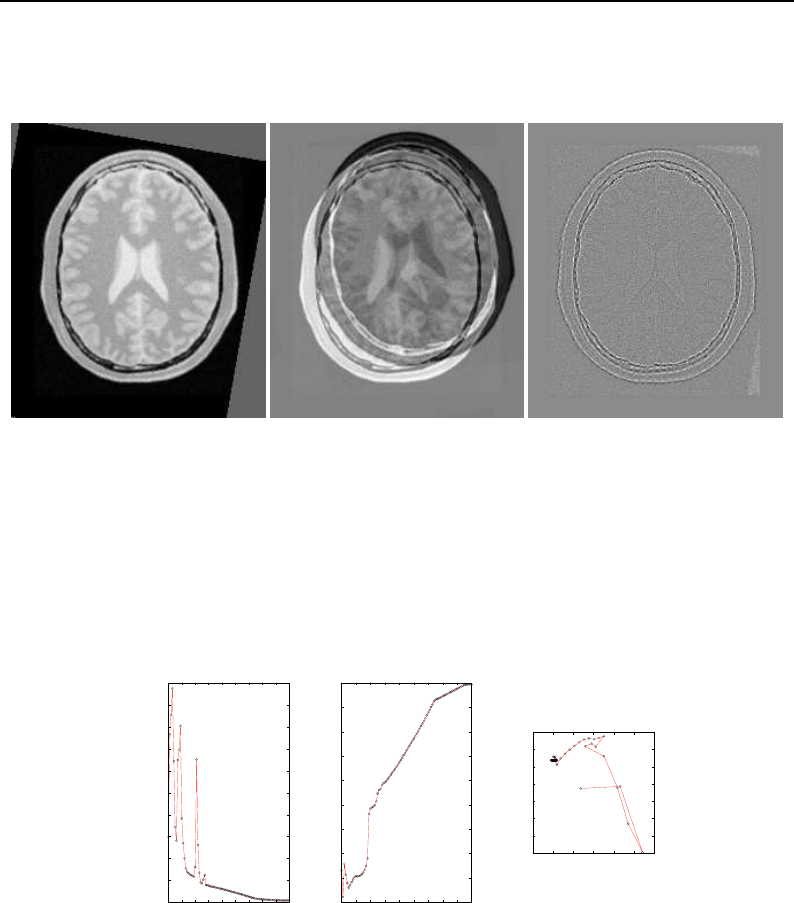

The Insight Toolkit (ITK) is an open-source, cross-platform system for medical image processing. It

provides medical imaging researchers with an extensive suite of leading-edge algorithms for

registering, segmenting, analyzing, and quantifying medical data. It is used in thousands of research

and commercial applications, from major labs to individual innovators.

The National Library of Medicine Insight Segmentation and Registration Toolkit, shortened as the

Insight Toolkit (ITK), is an open-source software toolkit for performing registration and segmenta-

tion. Segmentation is the process of identifying and classifying data found in a digitally sampled

representation. Typically the sampled representation is an image acquired from such medical instru-

mentation as CT or MRI scanners. Registration is the task of aligning or developing correspondences

between data. For example, in the medical environment, a CT scan may be aligned with a MRI scan

in order to combine the information contained in both.